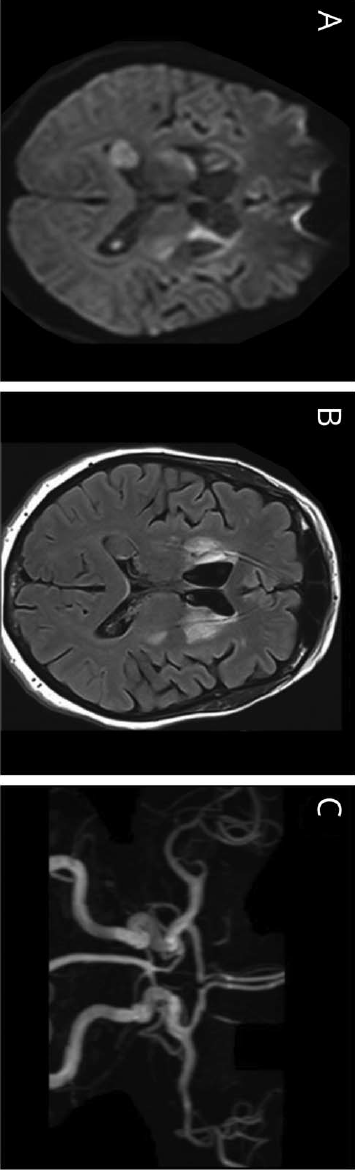

52岁,女性。

3周前进展性情绪异常,认知功能下降。因连续3次短暂性右侧偏瘫就诊。

MR DWI(A)、Flair(B)和TOF MRA(C)显示双侧纹状体和左侧放射冠急性和亚急性缺血性病变,MRA(C)未见近端动脉闭塞或狭窄:

基于高分辨率黑血增强T1脂肪饱和加权血管壁成像平扫:

钆强化MR显示颈内动脉末端和双侧MCA同心圆强化:

因怀疑原发性中枢神经系统血管炎开始给予激素治疗,3个月复查强化消失: